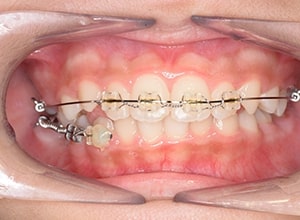

| 使用装置 | 0.018" × 0.025" standard edgewise | ||||||

| その他装置 | - | ||||||

| 口腔内ゴムの使用 | - | ||||||

| 批評・予后 | 右下5及び7の萌出前に右下6を整直させることによって、右下5の自然萌出が可能となり正常咬合への咬合誘導が行えたと思う。 |